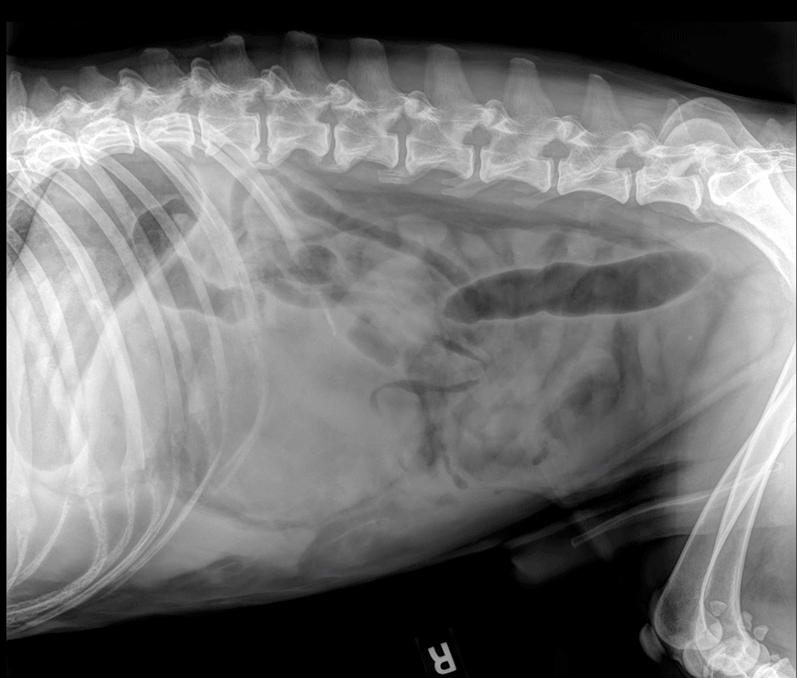

Photo courtesy Kendra Freeman

A 12-year-old male neutered husky presents for decreased appetite.